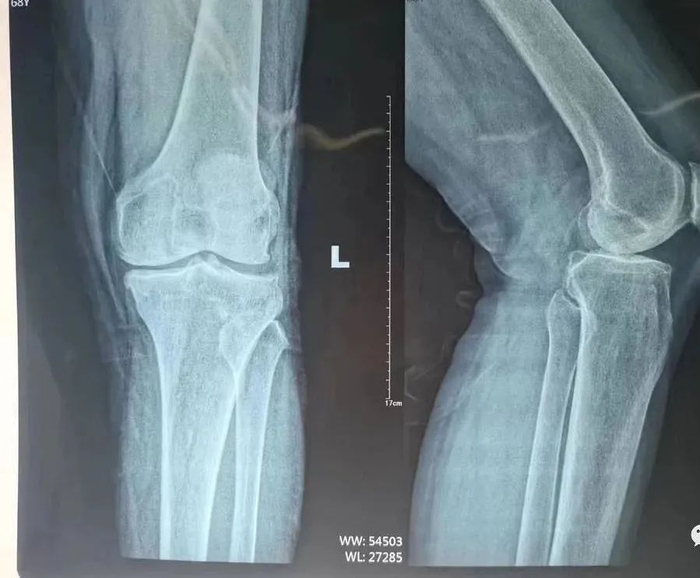

术前片